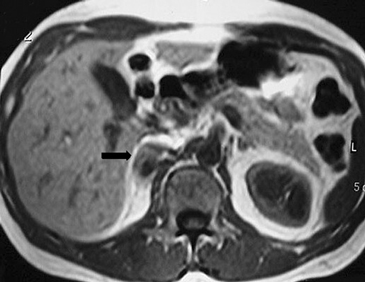

En la TC no contrastada las glándulas suprarrenales normales son homogéneas y simétricas, con una densidad muy similar a la del parénquima renal adyacente (Figura 1 a). Con un medio de contraste ev la glándula suprarrenal se opacifica en forma homogénea, similar al hígado o al bazo (Figura 1 b). Si la cantidad de tejido adiposo retroperitoneal es abundante las glándulas suprarrenales pueden aparecer enteramente rodeadas por grasa y su delimitación es más fácil (Figura 2 a); lo inverso ocurre en pacientes muy delgados con escasa grasa retroperitoneal (Figura 2 b). En RM, en secuencias ponderadas en T1 y T2 convencionales tienen una intensidad de señal homogénea, hipointensa respecto de la grasa adyacente e iso o hipointensa con respecto del parénquima hepático (Figura 3 a y b). En los cortes coronales se aprecia mejor la forma y la posición de las glándulas suprarrenales (Figura 3 c).

Figura 3. Glándula suprarrenal normal en resonancia magnética. (a) Cortes axial ponderado en T1 la señal de la glándula normal (flecha negra) es hipointensa respecto a la grasa retroperitoneal e isointensa respecto al parénquima hepático. (b) Cortes axial ponderado en T2 en que se muestra la glándula suprarrenal derecha (flecha blanca) y (c) corte coronal ponderado en T2 en que se muestra la glándula suprarrenal derecha (flecha blanca) y la glándula suprarrenal izquierda (flecha negra) con similares características de intendidad de señal. 3. Causas y prevalencia de las lesiones suprarrenales